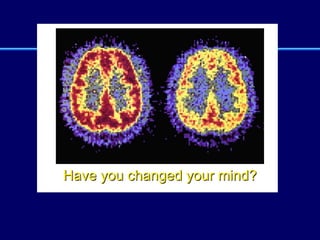

Have you changed your mind?

Have you changedyour mind?

• #67 Slide 14: Have you changed your mind? Here is our last slide. As we look at side-by-side PET scans of a person who has never used cocaine compared with a cocaine addict, can you tell which brain is more active and healthy? Take a guess. Yes, the brain on the left with an abundance of red is the healthy, active brain. With a little bit of knowledge about what drug addiction actually is, anyone —not just neuroscientists and neurobiologists—can see the changes in brain activity caused by drug abuse and addiction. The PET scans we’ve looked at today prove that. We’ve seen the scientific facts. We’ve learned that addiction is a brain disease. And we’ve also learned that scientists are making great strides in developing treatments for addiction. There will be no magic charm to make addiction go away. But educated and informed with the scientific facts about what drugs can do to the brain, we are each in a better position to decide whether or not to take drugs in the first place. Given the facts, have you changed your mind? Photo courtesy of NIDA. If You Change Your Mind. Student magazine. NIH Publication No. 93-3474, 1993.